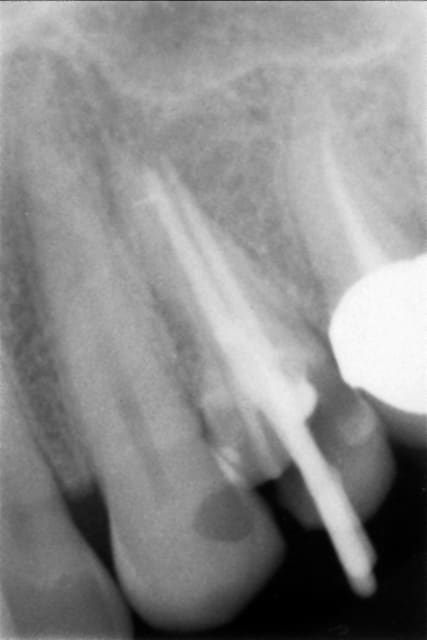

Bon mon numéro 3 est plus énigmatique.

Patient 37 ans, pas de souci médical, perf de racine distale de 47 par tenon radiculaire...

- Extraction le 5/05/10

- Alvéolite suppurée, traitement par mèches eugenol

- à j+7, mise en place d'ALVOGYL, car le patient part en vacances

- à 2 mois : je vais pour clouter, le site est toujours plein de fibres d'alvogyl non résorbée...

Bref, je pleure et referme.

- à 6 mois : implantation d'un inkone 5.5/8.5

- période d'ostéointégration : du 30/11 au 30/03 (prudent)

-> fibrointégration

- dépose illico et re-pose à 6 semaines, ça roule aujourd'hui.

Bon, honnêtement, je trouve que je l'avais mal posé, il était pas assez enfoui, et j'avais laissé des remparts osseux trop fins...

Mais bon, on ne peux exclure de me dédouaner en accusant un état de surface, c'est gentil de votre part si vous y penser.

4 mois cicat aeypek - Eugenol

Preop xzbkyt - Eugenol

Postop snyv55 - Eugenol